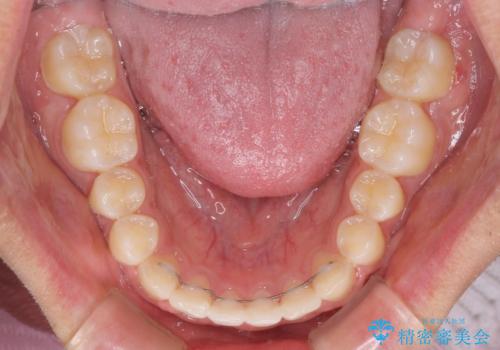

今後はすり減ってしまった歯の形をセラミッククラウンで改善したいとのことで、クロスバイトが改善し咬みやすくなった時点で装置を外すこととしました。

1年で治療を終えることができ、患者様には大変満足していただきました。